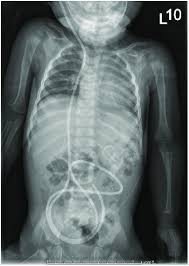

Vp Shunt Patient Presenting With Increasing Abdominal Girth And Pain Download Scientific Diagram